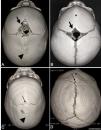

Data collectionThe authors of the present study assessed data from the medical records of the hospital and private clinic where the interventions of the patients with CS ensued, such as age at attendance, sex, and those that warrant no exclusion factors. In addition, the patients’ images were obtained in the DICOM format and transferred to the OsiriX imaging program (OsiriX, Geneva, Switzerland),19 which was validated using ANVISA to ensure the use of the medical findings. The images were assessed by the senior author of this study, who assessed the normality of the brain and analyzed the skull surface using the 3-D reconstruction images in accordance with the following parameters: (1) if the AF was open or closed (open, all visible AFs independent of the size; closed, completely ossified or no fontanel in spite of all the sutures remaining open) and (2) the type of CS (Figure 1 and 2).

Computed tomography image with three-dimensional reconstruction of the skull image in children with non-syndromic craniosynostosis, demonstrating that anterior fontanel (AF) could present as open (thick black arrow) or closed (thin black arrow). (A) A widely open AF is depicted in patients with (A) scaphocephaly and (B) trigonocephaly or (C) a completely fused AF in scaphocephaly and (D) trigonocephaly. The metopic suture is fused in trigonocephaly (*). The sagittal suture is fused in the scaphocephaly (arrowhead).

This discrepancy in AF closure pattern between patients with trigonocephaly and those with scaphocephaly reveals the different directions of suture fusion in the two conditions. Indeed, in most children with scaphocephaly, fusion begins on the posterior segment of the suture toward the AF. During diagnosis, due to the abnormal skull shape, the AF remains completely open. Otherwise, the metopic suture starts to close in the proximity of the AF, which greatly impacts early closure. This directionality of fusion was corroborated by Lottering et al.,26 who investigated the temporal closure of AF in 256 healthy children aged <30 months by using multislice cranial CT scans and observed the posteroanterior pattern of sagittal suture ossification and metopic closure near the AF and the coronal sutures synchronously.

To the best of our knowledge, a major risk is the misdiagnosis of the absence of CS based on the perception of a widely open AF. This false-negative interpretation might have occurred in 30% of our sample, and half of the patients who presented with an open AF had CS (Figure 2). Thus far, no information regarding this fact is available in the literature, and the authors surmise that the risk is crucial in cases with scaphocephaly. Therefore, pediatricians should be aware of this fact and focus on the existence of skull deformities that are characteristic of CS to reduce the possibility of a misdiagnosis.